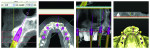

The implant planning for the initial implant placement was viewed in the SimPlant planner (Figure 6 though Figure 10) and MIS’s SEVEN® implants (www.mis-implants.com) were chosen for placement due to their cost effectiveness; sand-blasted and acid-etched surface, which increased the surface area; sterile single final drill; and implant stability at placement. The placement of five additional implants post-edentulation and mandibular ridge leveling can be seen in the SimPlant full window view. The SimPlant treatment plan was designed to address the edge to edge anterior bite. This would be done by performing an osteoplasty of the mandibular anterior and placing the implants in a more uprighted position with respect to the existing mandibular dentition. Placement of implants inferiorly and lingually would allow for a modification from a splayed Class III to a Class I occlusal relationship. The removal of the anterior teeth combined with osteoplasty and implant placement in a more inferior position would allow for maintaining her existing vertical dimension of occlusion. The patient agreed to the cost and number of implants, but she was given the option to leave the remaining lower teeth and place smaller-diameter implants in the posterior regions, so a treatment variation was created for this scenario as well. She wasn’t certain whether she could approve full mandibular edentulation until she evaluated the initial procedure’s success. Lastly, the maxillary full-arch treatment was planned to facilitate phase 2 treatment and provide her with an upgrade path.7

Working with Limited Vertical Dimension

Zest Locators (ZEST Anchors, www.zestanchors.com) were chosen for placement on implants 21 and 22 to retain the lower partial denture (Figure 20). The proper locator heights were selected by measuring from the top of the tissue to the platform of the implant after suitable healing. This number would normally be adequate, but due to the limited interocclusal space, 1 mm was subtracted to keep the locator head as close to the tissue as possible (Figure 21). The laboratory was instructed to place the male of the locator into the frame of the denture, and a tooth-colored acrylic was used as a facing for the teeth so that a minimal dimension of acrylic could be used, but it was still supported by the metal framework of the partial for strength (Figure 22).

The modification of the bridge to accept a removable partial denture was performed, as the maxillary implant rehabilitation would be postponed indefinitely. The upper partial, which was designed with a plate design, had rests, clasps, undercuts for clasps, and a bilateral balanced occlusion to decrease occlusal overload to the implant bridge and mandibular implants. Use of the bridge to retain the partial would further provide stability, support, retention, and cross-arch stabilization for the maxillary prosthesis (Figure 23).